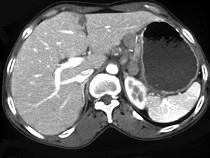

问题 女,56岁,上腹部钝痛、腹胀不适1月余,纳差、消瘦,影像检查如图,最可能的诊断是()

选项 A.胃幽门管溃疡 B.胃腺癌并幽门狭窄 C.胃淋巴瘤 D.胃间质瘤 E.胃恶性间质瘤

答案 B